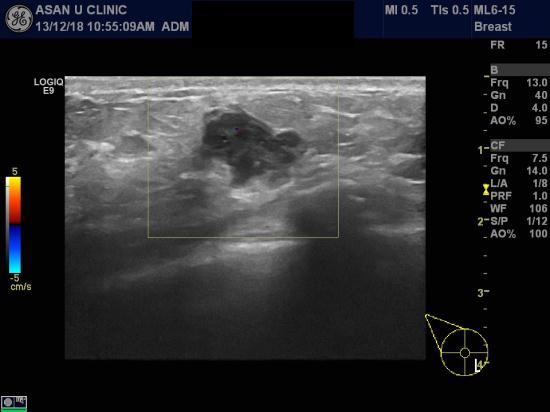

아산유외과 개원 후 46번째 유방암진단.

우측 유방에 하내측에 만져지는 몽우리 있어 내원하신 41세 여성분입니다.

초음파상 1.69cm 장경의 혹이 있어 중심핵생검으로 침윤성 유방암 진단되셨습니다.

2012년 9월 공단검진상 특별한 소견이 없어서 방심한 가운데

2014년 공단검진 전에 유방암이 진단되신겁니다.

공단검진사이에도 증상이 있다면 유방암 검진을 해보실 필요가 있습니다.